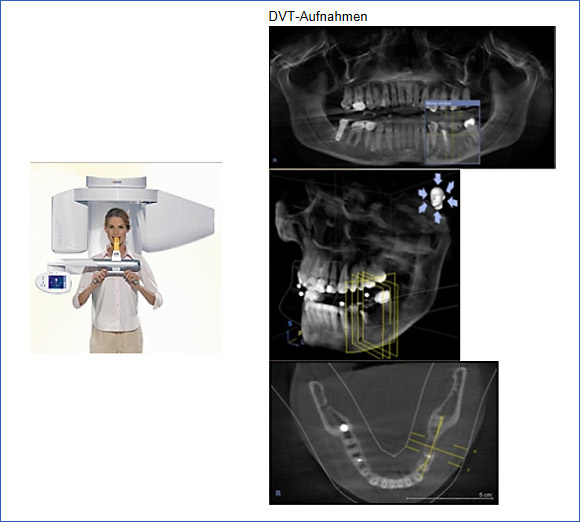

Volumentomograph (DVT)

Vorteile dieser Aufnahmetechnik:

Die Aufnahme ist sehr strahlenschonend mit bis 75 % Ersparnis von Röntgenstrahlen gegenüber den CT-Aufnahmen. Die Schnittbilder vom Oberkiefer und Unterkiefer werden mit einer einzigen Aufnahme erstellt und können direkt am Computer betrachtet und ausgewertet werden. Damit sind alle anatomischen Strukturen wie Kieferhöhlenaus- dehnungen, Nervnähe, Entzündungsherde für einen notwendigen chirurgischen Eingriff klar erkennbar.

Für die Planung einer Implantatsversorgung stellt diese Aufnahmetechnik die beste und sicherste Methode dar.

Die Aufnahme erfolgt außerhalb unserer Praxis, die Auswertung in unserer Praxis.